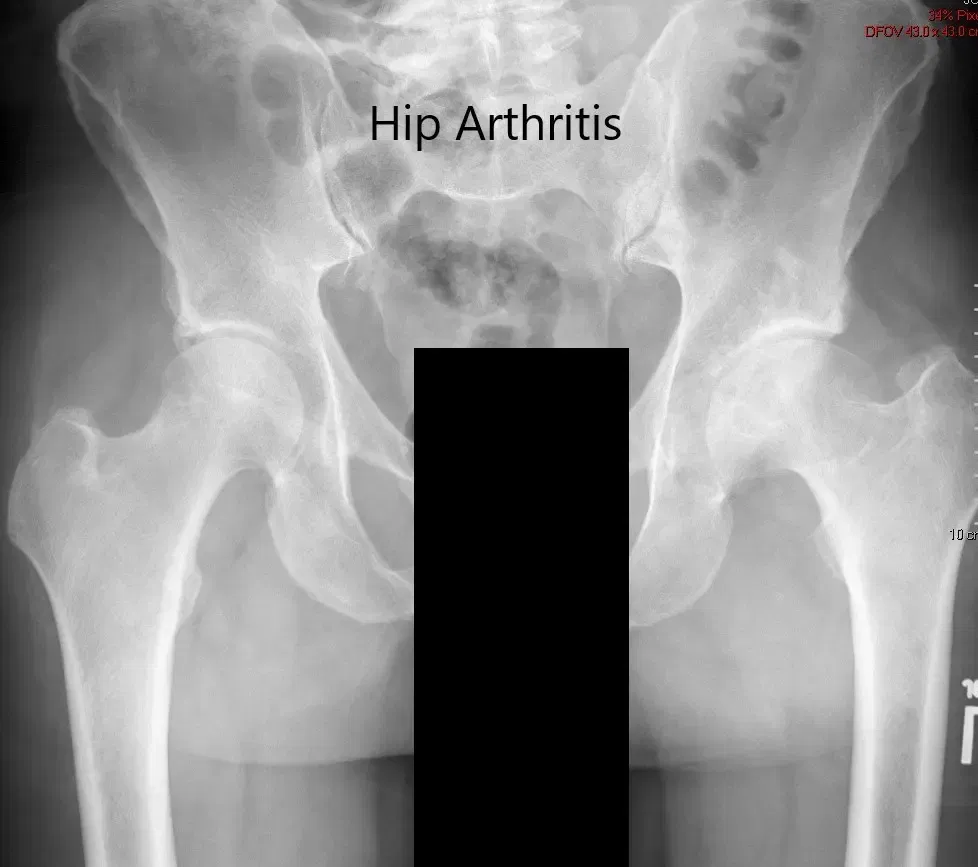

Imaging revealed severe osteoarthritis of the left hip with subchondral cysts, sclerosis, and osteophytes. The left acetabulum was shallow with a shortened left femoral neck.

Preoperative X-ray of the pelvis showing AP view of the pelvis with both hips.

Preoperative X-ray of the left hip in AP and frog-legged lateral views.